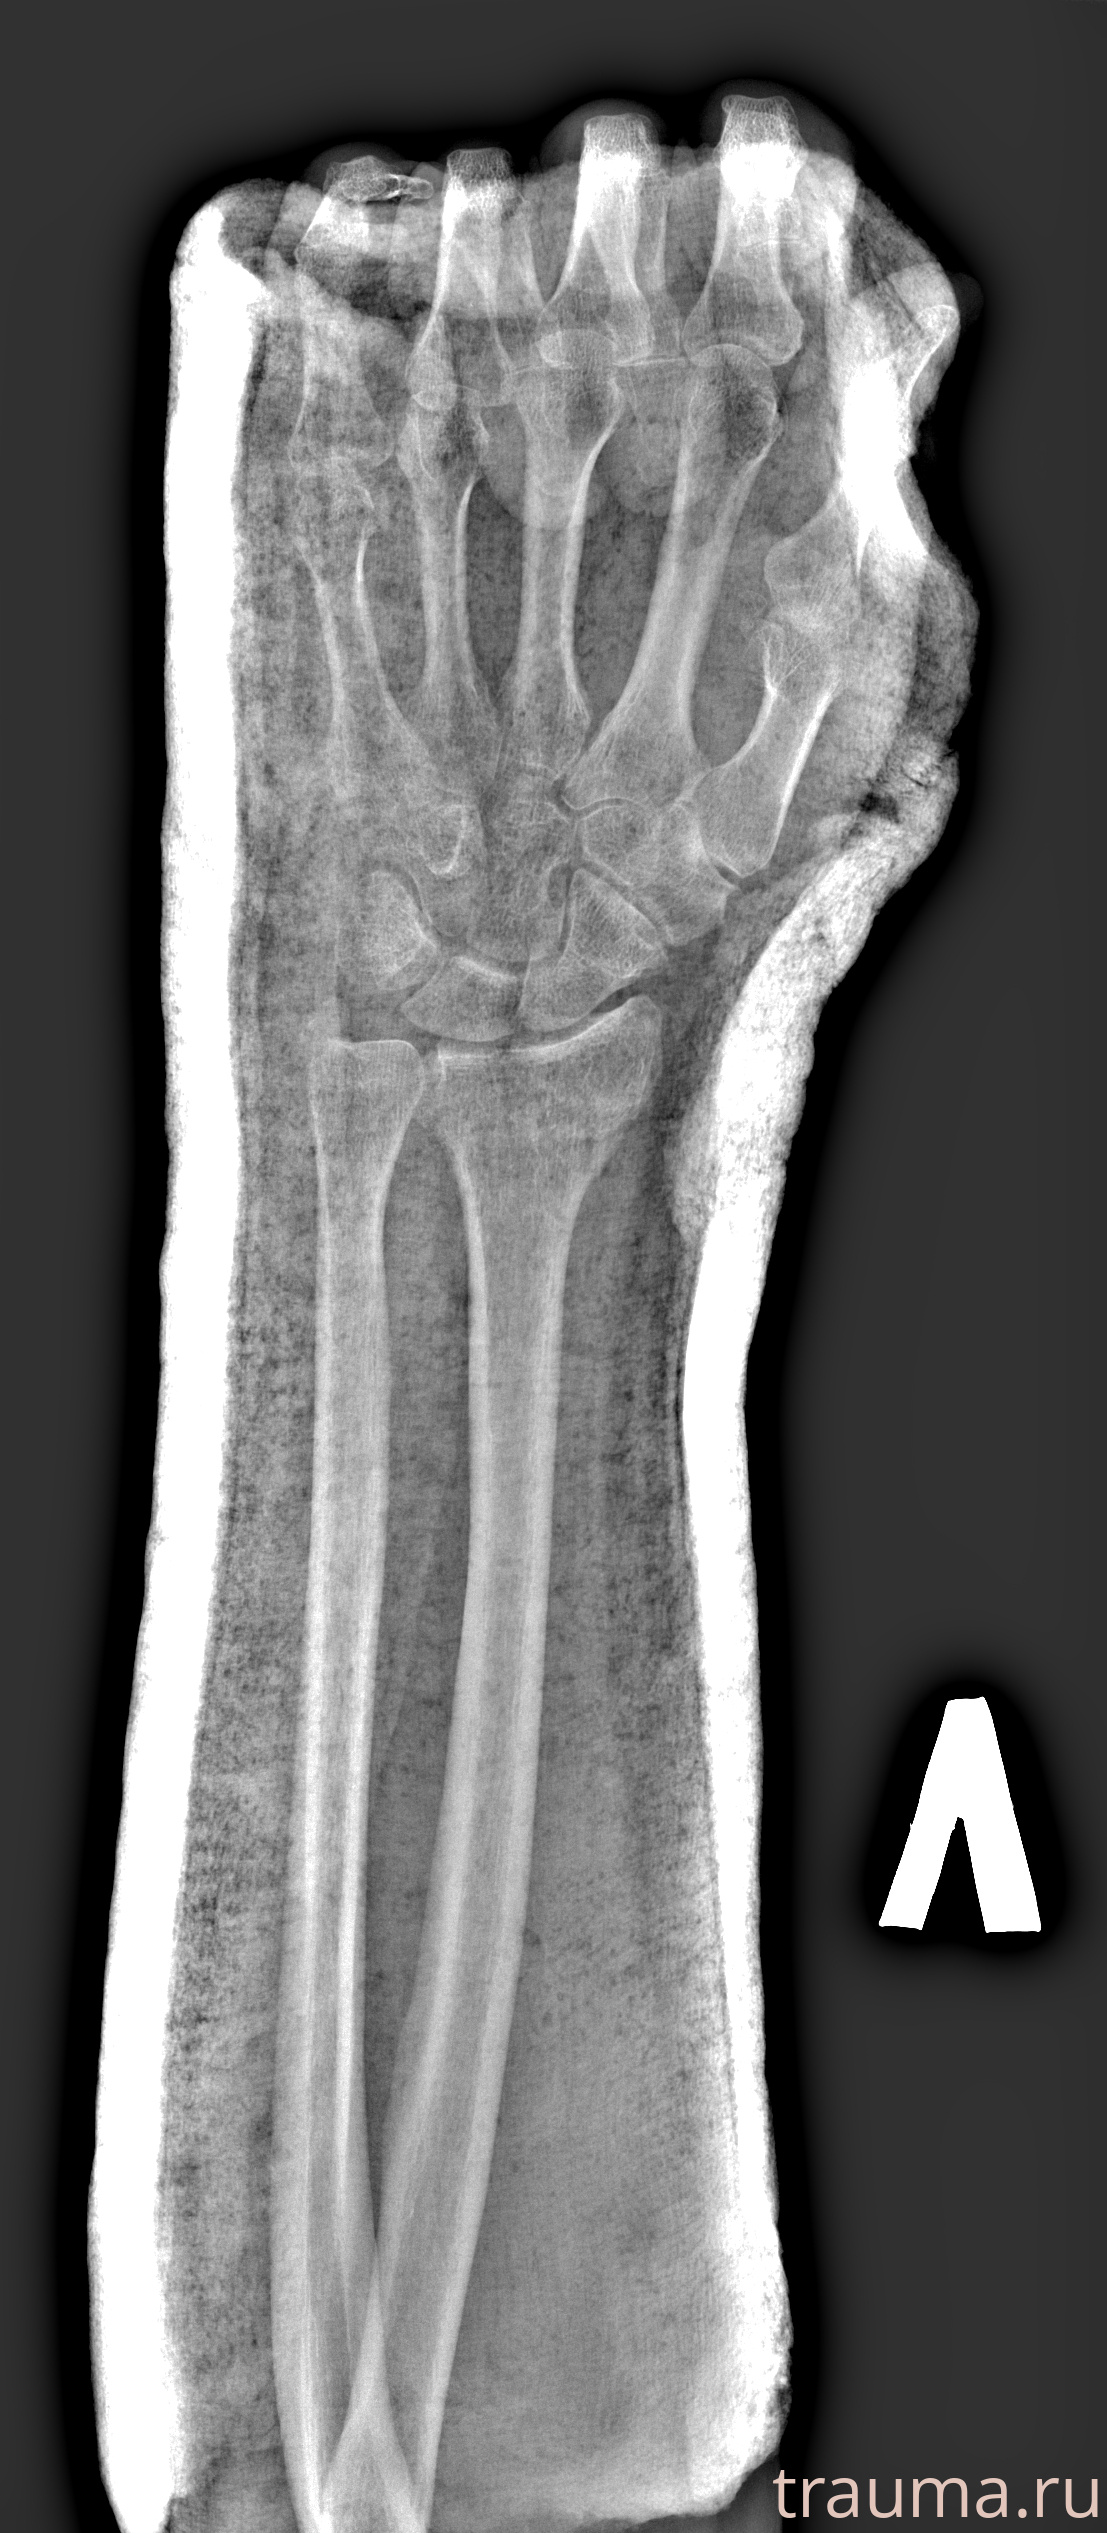

Рентгенограммы

Рентген на дому: по вашему адресу приезжает врач-рентгенолог, травматолог-ортопед с мобильным рентгеновским аппаратом, проводит диагностику травмы или заболевания, делает необходимые рентгенограммы, дает рекомендации по дальнейшему лечению. Получить качественные снимки в домашних условиях возможно благодаря уникальной методике, разработанной МосРентген Центром для института  Склифосовского